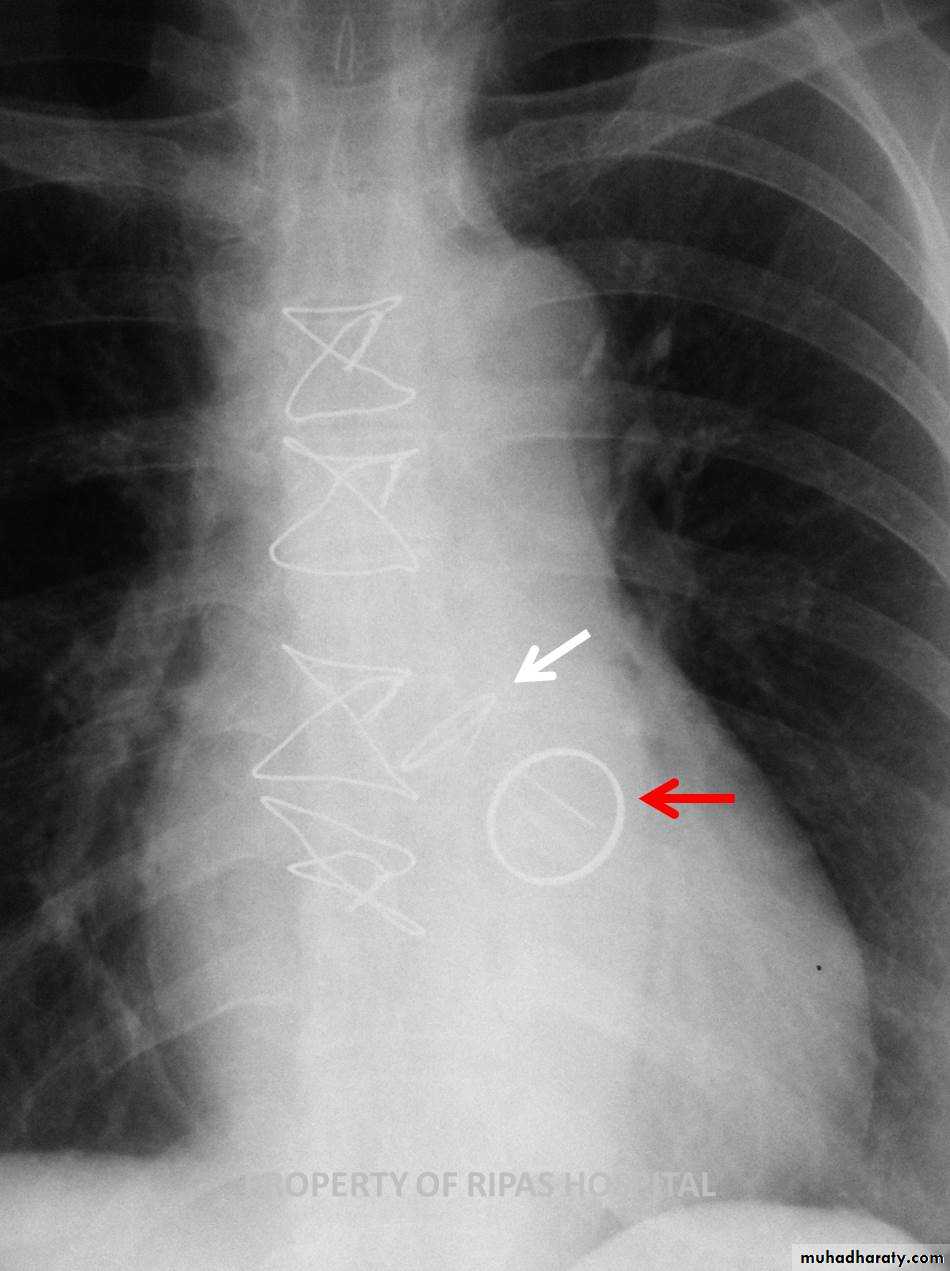

Fall from the 2nd floor